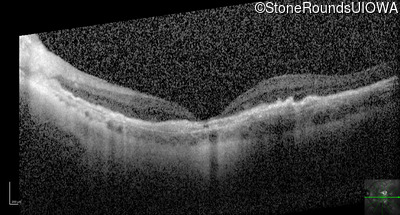

Optical Coherence Tomography - Right - 20/160 -2

Exemplar / OCT Stack